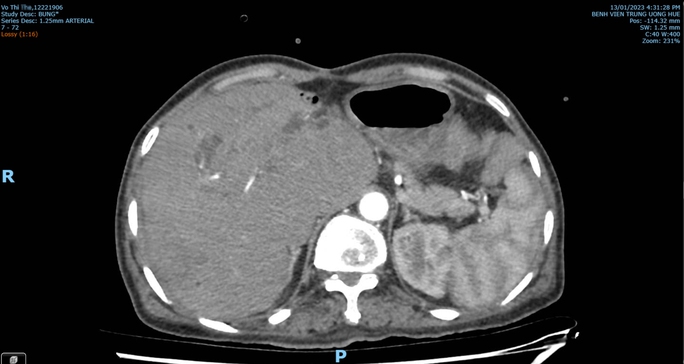

Bà Th. nhập viện vào cuối tháng 12-2022 với tình trạng sốt cao, đau hạ sườn phải. Kết quả CT Scan bụng cho thấy hình ảnh áp-xe gan và khối giả phình động mạch ở gan phải.

Kết quả chụp CT Scan bụng lại, nội soi kiểm tra tính chất mật chảy qua bóng Vater khẳng định được bệnh nhân bị vỡ giả phình động mạch gan nên được hồi sức tích cực, can thiệp nút động mạch gan chọn lọc qua da cấp cứu thành công.